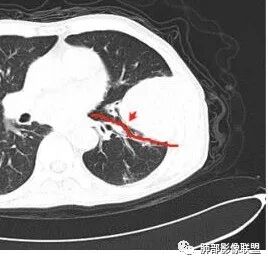

鳞癌,与吸烟关系密切,起源于支气管粘膜上皮,典型的征象就是支气管截断,周围型鳞癌往往体积较大,有时候与支气管关系不好判断,需要多平面重建看支气管的关系。

鳞癌因为侵袭性力较强,容易直接侵犯胸膜、胸壁,而周围型肺癌侵犯胸壁的90%癌肿是鳞癌,这也是鳞癌的一个特征性表现。邻近胸壁的脂肪层消失,胸壁肿块形成或有肋骨皮髓质边界不清的侵蚀破坏(而非边缘硬化或崩解)是瘤体向周围直接侵犯的可靠征象。

鳞癌因为破坏力强,其内可见灶样坏死区,坏死边界不清,其内血管破坏彻底。

肉瘤样癌也好发于中老年人,与吸烟关系密切。肿块体积往往较大,也是好发于胸膜下伴胸壁侵犯,也容易发生坏死,与周围型鳞癌的主要鉴别点在于支气管的关系和病灶内强化的情况。肉瘤样癌以环状强化为主,病灶周边多以癌组织为主,血供丰富,病灶中心区则以肉瘤成分为主,血供较差,易出现粘液样变性、坏死、出血,坏死边界清楚。

肺肉瘤是少见的来源于间叶组织来源的肿瘤,起源于肺间质、支气管壁、支气管软骨等间叶组织,往往体积较大,边缘光整,无明显分叶、毛刺,也会大片坏死,也会有胸壁的侵犯,有时与肺癌、肉瘤样癌很难鉴别。